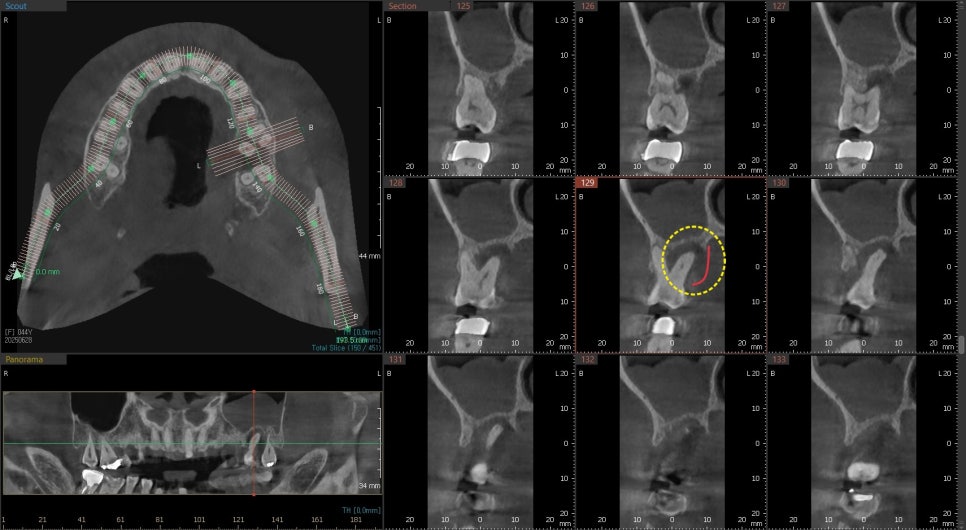

이렇게 사진상 진단시는 발치와 동시에 임플란트 수술이

가능했지만 제때 치료 시기를 놓치게 되면

시간이 지나 주변 뼈들이 염증에 의해 더 녹아

발치 후 치조골이식을 진행한 후

회복후 수술이 필요한 경우도 있습니다

노란 원으로 표시된곳이 치조골이식후 회복된상태입니다

3D CT를 촬영해보니

가장 큰 뿌리 주변이 염증에 의해 뼈가 녹아있습니다

빨간선으로 표시된부분이 뼈로 채워져 있어야하지만

어둡게 보이는것은 염증으로 뼈가 녹았다는것을 보여줍니다.

이런경우 발치와 동시에 즉시 임플란트 수술이 가능은 하지만 추후 뼈가 어디까지 회복될지 예측이 어려웠기 때문에 발치를 했던 주변으로 치조골이식을 해서 볼륨을 유지시켜주는것을 발치와 보존술이라고 합니다

약 4개월후 빨간선으로 표시된것 처럼 주변 뼈들이 회복이 된것을 확인 후 임플란트 수술이 진행되었습니다.